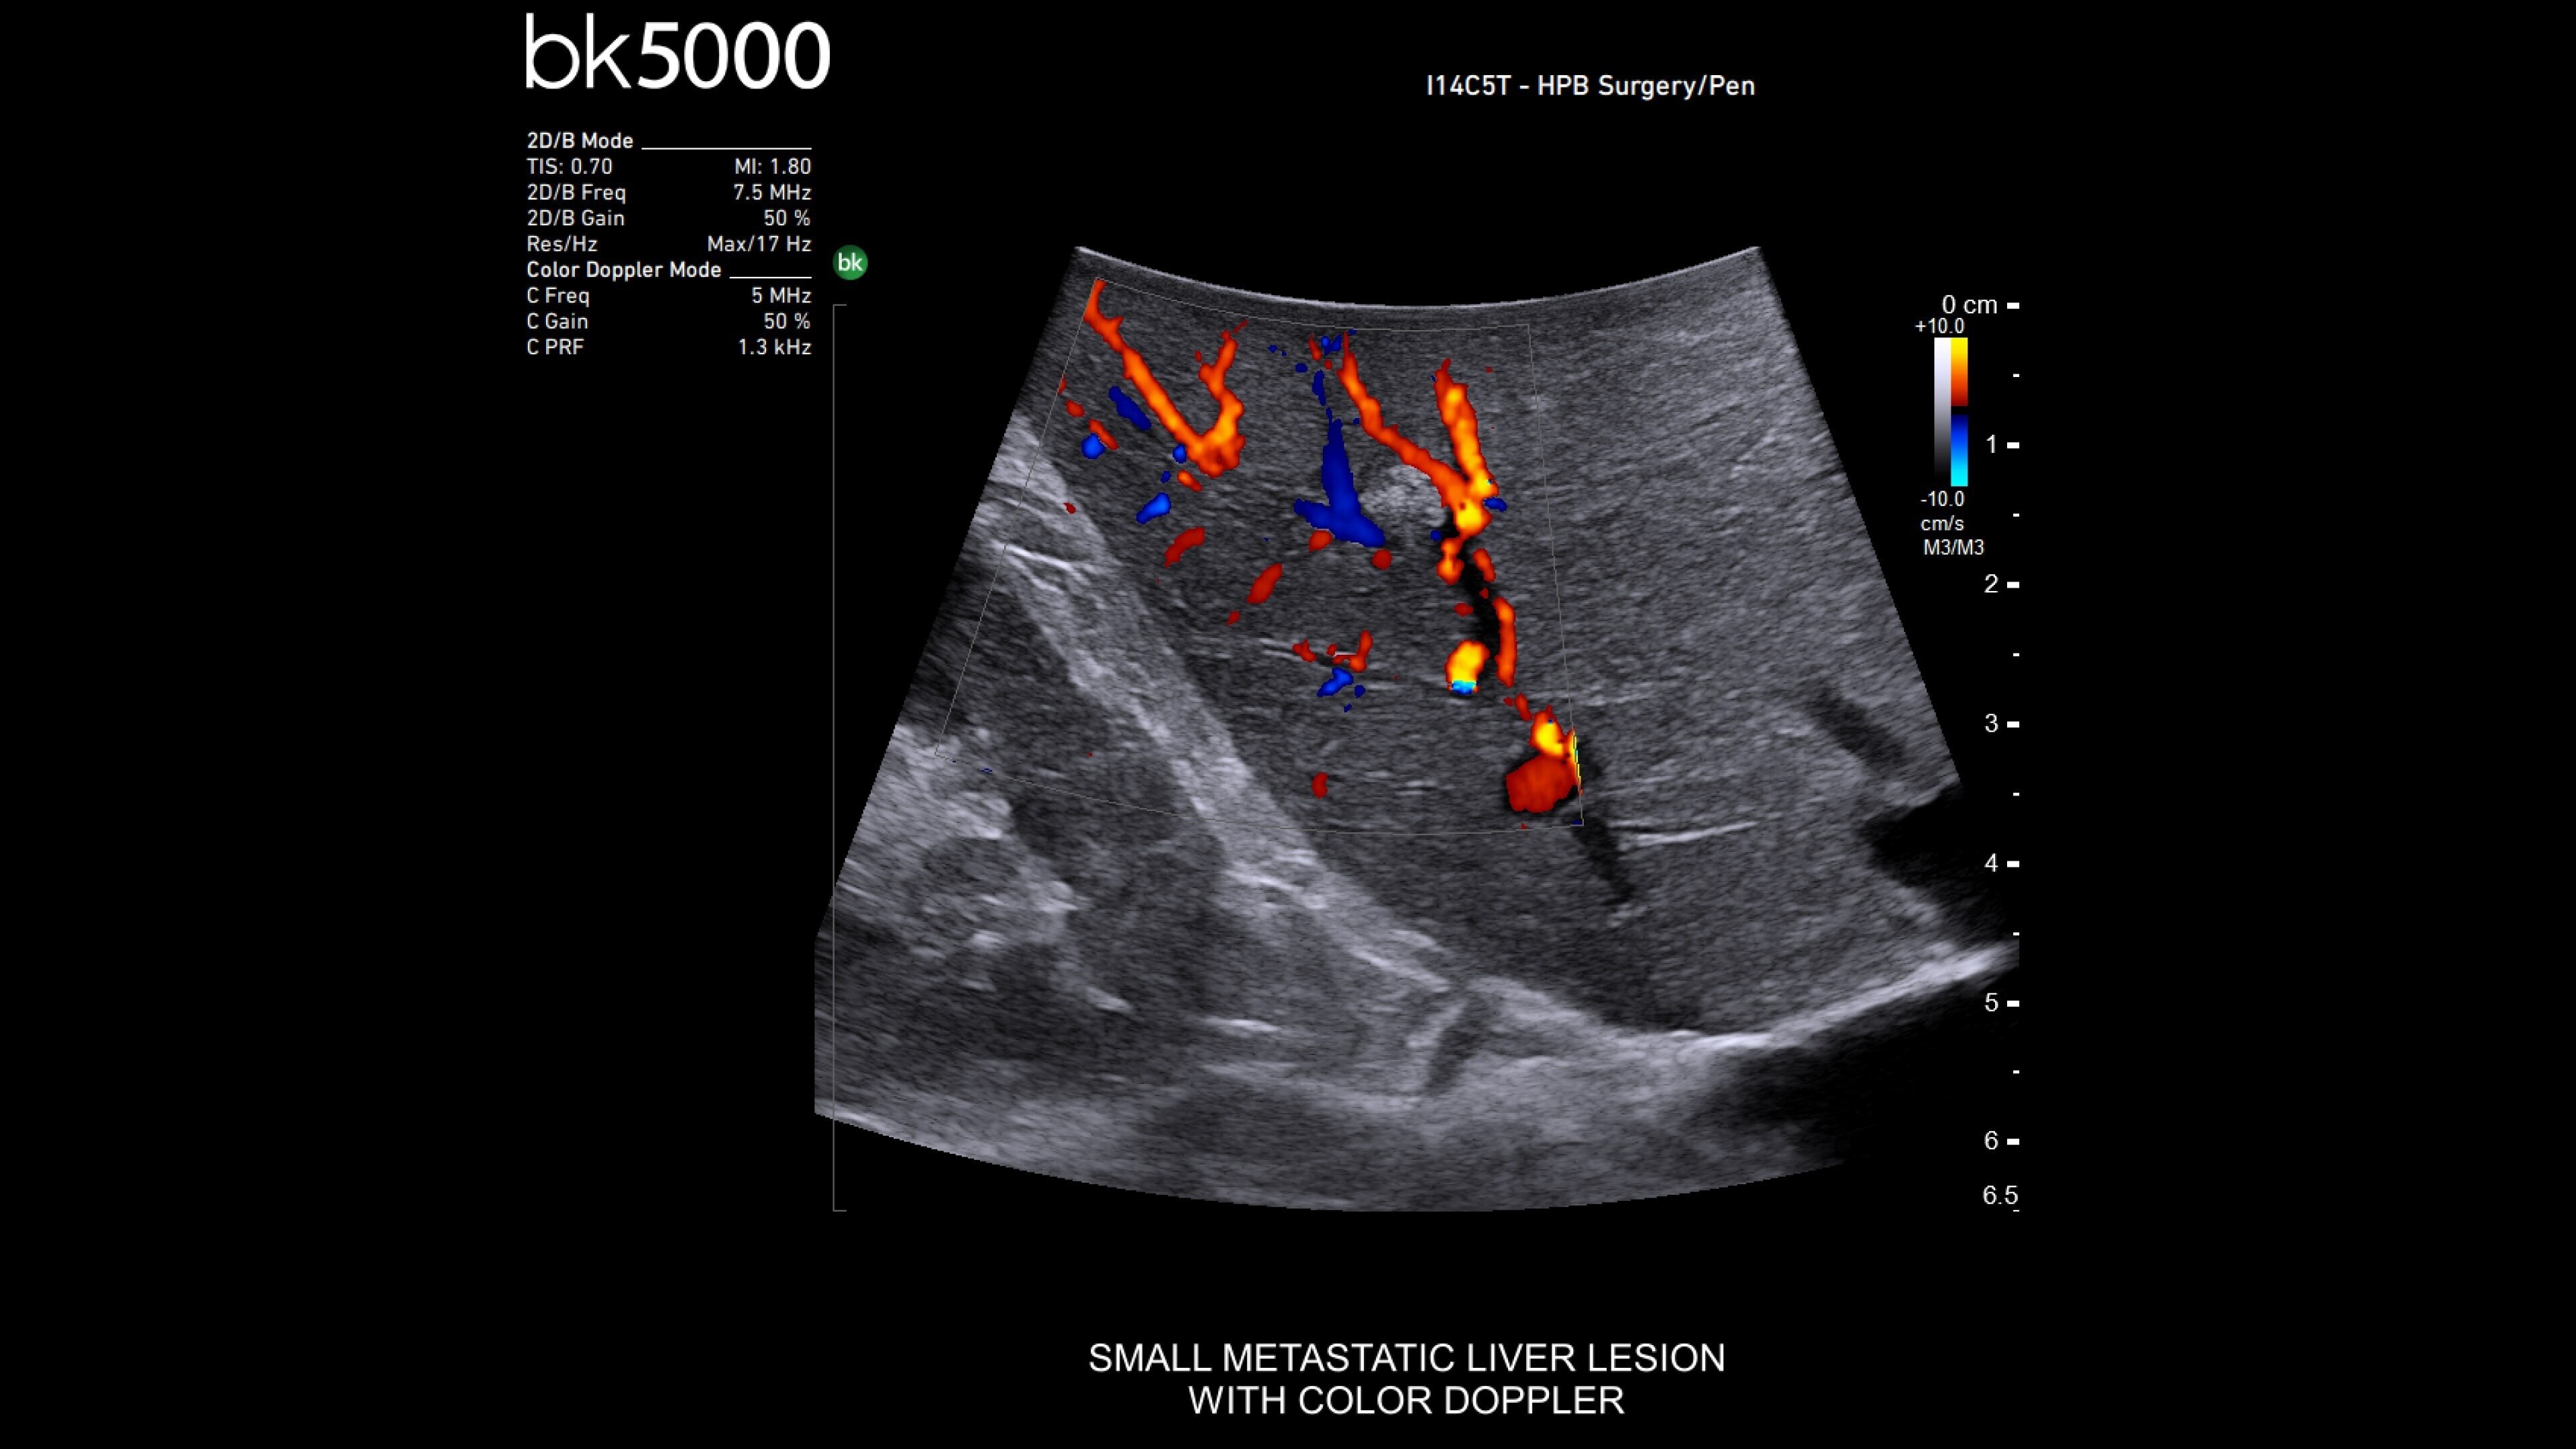

The bkActiv is a high-performance imaging system offering detailed, real-time surgical visualization. Refined through extensive research and user feedback, it supports remarkable imaging of areas of interest–neurosurgical (neuro-oncology, spine, neurovascular), urology (prostate, kidney, and bladder), hepatobiliary, colorectal, and pelvic floor.

It features technology such as Dual Live Compare for live image comparion, stored image compare, mirror image to see a live iUS image on the touch screen and sensitive color Doppler visualizes blood flow during complex surgeries.